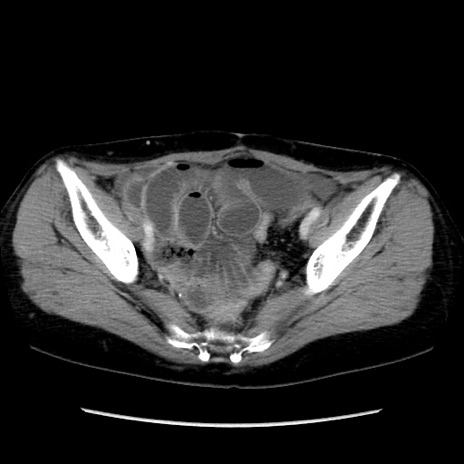

冠状断像